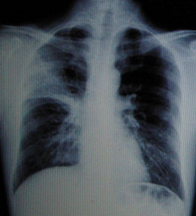

男性,40岁。发热4天,伴黄痰。

A.右上肺不张

B.右上肺炎

C.右上肺癌

D.右上胸膜肥厚

『正确答案』B

男性,23岁,午后低热2周。

A.左上肺炎

B.左上支气管扩张

C.左上浸润型肺结核

D.正常胸片

『正确答案』C